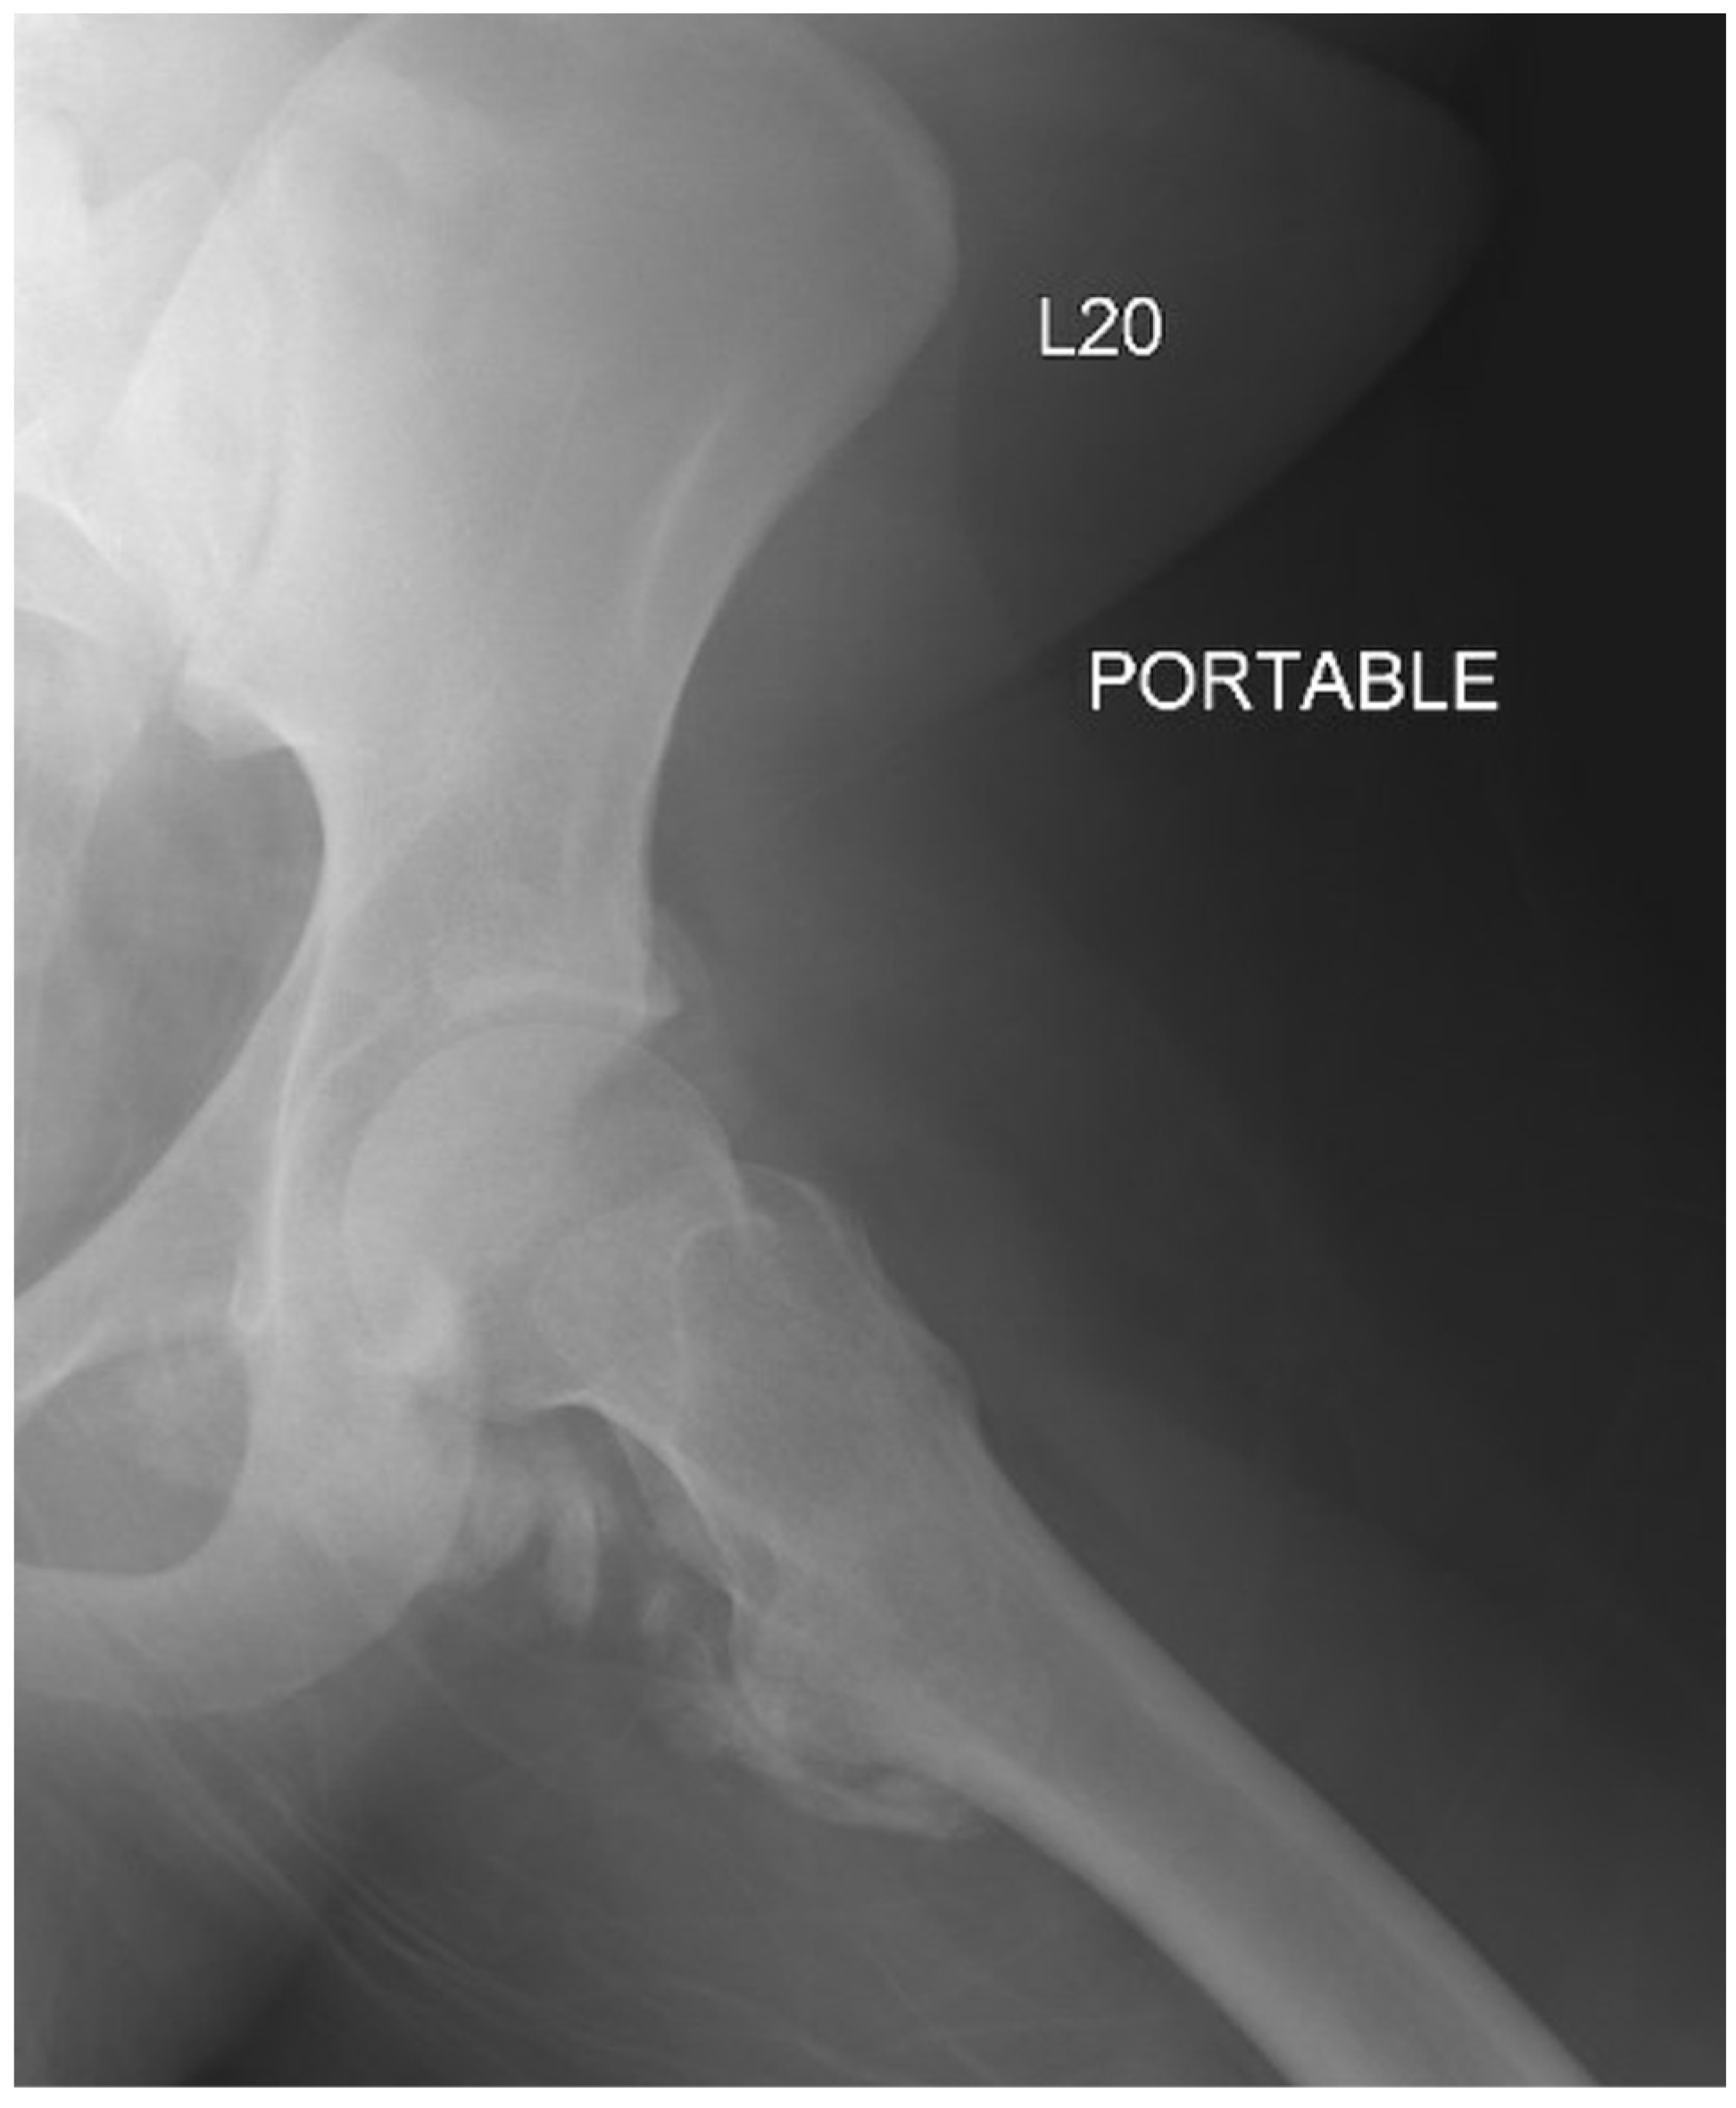

2. Case Report